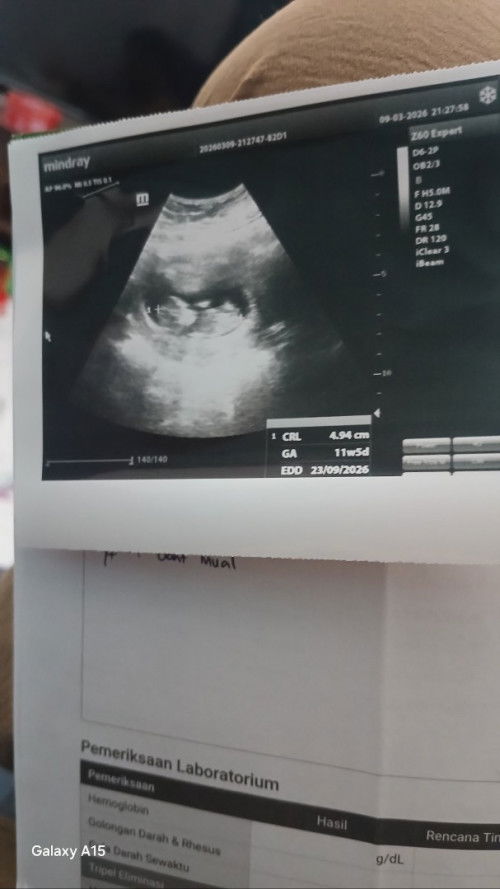

#bantujawab kalau usia 9w tidak ada janin apakah harus langsung dikuret ya? soalnya kata dokter harus kuret tapi beneran masih kaget 🥲